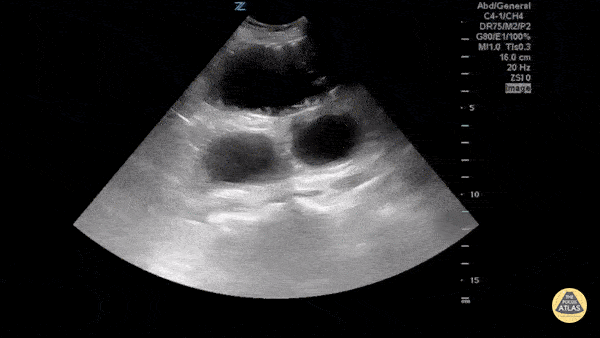

Visualized here are dilated loops of bowel as a result of SBO. One can see hyperechoic fecal material moving to and fro due to blocked peristalsis, visible plicae circularis (folds of small bowel mucus membrane that increase surface area for absorption) also known as the "piano sign," and abdominal free fluid between loops known as "tanga sign." Sukh Singh, MD